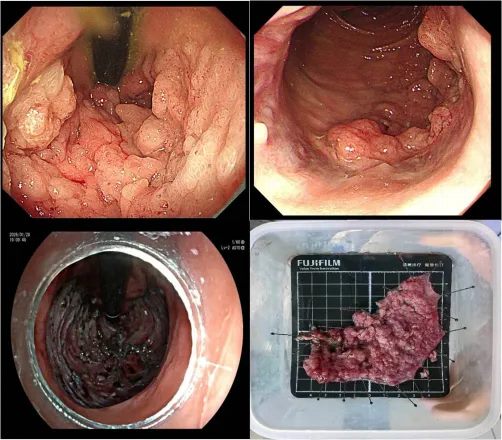

手术在麻醉团队的护航下展开。梅璐副主任医师操作高清电子肠镜,清晰观察肿瘤范围与边界,精细标记后,使用高频黏膜切开刀逐步切开并剥离病灶。肿瘤体积大、血供丰富,且直肠黏膜薄、操作空间狭小,对术者的经验与技巧提出极高要求。团队凭借精湛技术,在4小时内将约11cm×11cm的肿瘤完整剥离,术中出血仅20ml,未损伤肛门括约肌及周围重要结构,无并发症发生。术后病理证实切缘阴性,达到临床治愈。

640 (3)_副本